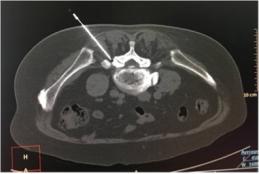

腰椎间盘突出是指椎间盘形态发生局部性向外扩张改变而引起临床症状的损伤类型。它是椎间盘变性不均匀、不对称, 纤维环部分区域几乎全层断裂所造成。

腰椎间盘突出压迫神经根会出现下肢麻木疼痛,压迫交感神经会出现下肢血管收缩导致下肢发冷,发凉,感觉变差。